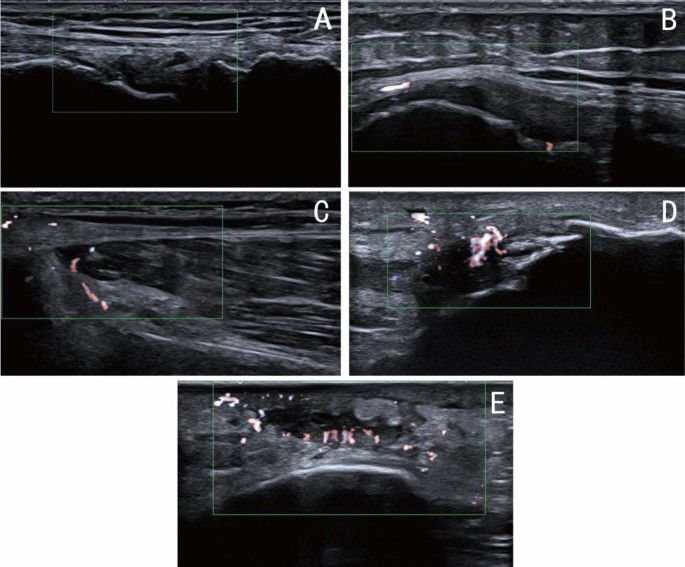

Figure 6 displays ultrasound images (A–E) of five patients with varying pathological conditions, with green rectangular boxes identifying the target regions. These images highlight the distribution of blood flow across different anatomical sites and their pathological features. Grading was performed based on blood flow signal density, synovial characteristics, joint effusion, and the severity of soft tissue lesions, revealing a progressive trend from mild to severe (A as grade 0, B as grade 1, C as grade 2, and D and E as grade 3).

Blood Flow Signal Grading in Patients with Different Pathological Conditions (A) Ultrasound image of a patient graded as SMI level 0; (B) Ultrasound image of a patient graded as SMI level 1; (C) Ultrasound image of a patient graded as SMI level 2; (D and E) Ultrasound images of patients graded as SMI level 3.

Figure 6A illustrates effusion within the suprapatellar bursa and medial and lateral joint spaces of the left knee (measuring 2.33 × 0.48 cm, 1.66 × 0.38 cm, and 1.36 × 0.38 cm, respectively). Synovial thickening and reduced echogenicity suggest mild inflammatory changes in the synovium. The absence of significant blood flow signals indicates minimal vascular proliferation and mild osteoarthritis. Furthermore, thickening of the lateral collateral ligament with blurred fibrous structures suggests potential ligament injury. This case is classified as grade 0.

Figure 6B reveals effusion within the suprapatellar bursa (0.61 × 0.17 cm) and medial (0.84 × 0.30 cm) and lateral (0.58 × 0.34 cm) joint spaces of the left knee, along with synovial thickening and heterogeneous echogenicity, indicative of inflammatory changes. The presence of minimal blood flow signals suggests early active inflammation, with a noticeable increase in vascular activity compared to Fig. 6A. This case is assigned a grade of 1.

Figure 6C shows a hypoechoic region at the proximal attachment of the right gastrocnemius muscle, accompanied by a substantial presence of blood flow signals, indicative of localized strain. Blurred fibrous structures suggest mechanical damage coupled with localized inflammatory responses. The pronounced increase in blood flow signals reflects heightened dynamic inflammatory activity. Despite the localized nature of the lesion, the significant enhancement of blood flow signals justifies a grade of 2.

Figure 6D depicts effusion in the joint cavity and medial and lateral joint spaces of the left knee (0.98 × 0.23 cm, 0.81 × 0.38 cm, and 2.86 × 0.59 cm, respectively). Marked synovial thickening and reduced echogenicity are evident, indicative of osteoarthritic inflammatory changes. Edema in the soft tissue beneath the patellar edge, coupled with abundant and blurred blood flow signals, suggests notable alterations in synovial and soft tissue vascular supply. The extensive nature of the lesion and the active inflammatory response are consistent with a grade of 3.

Figure 6E demonstrates thickening and hypoechoic areas (3.03 × 0.88 cm) in the prepatellar fat layer of the right knee, accompanied by abundant blood flow signals. Effusion is observed in the suprapatellar bursa and medial and lateral joint spaces (1.76 × 0.32 cm, 1.23 × 0.28 cm, and 0.74 × 0.28 cm, respectively). The dense distribution of blood flow signals indicates pronounced inflammatory changes in the synovium and soft tissues, as well as joint cavity effusion, showing activity levels comparable to those in Fig. 6D. This case is classified as grade 3.

Differences, similarities, and severity assessment

All cases depicted in Fig. 6 display osteoarthritic characteristics, including synovial thickening, reduced echogenicity, and joint effusion, with varying degrees of enhanced blood flow signals correlating to different levels of inflammatory activity. Soft tissue abnormalities are also evident, such as ligament thickening in Fig. 6A, strain in Fig. 6C, and edema beneath the patellar margin in Fig. 6D, underscoring the link between osteoarthritis and soft tissue lesions. The primary variations are observed in the distribution and density of blood flow signals: Grade 0 (Fig. 6A) exhibits no detectable blood flow signals, indicating minimal inflammatory response; Grade 1 (Fig. 6B) reveals sparse blood flow signals, signifying early active inflammation; Grade 2 (Fig. 6C) shows localized but abundant blood flow signals; and Grade 3 (Fig. 6D and E) demonstrates densely concentrated blood flow signals, reflecting extensive active inflammation. Progression from Fig. 6A to Fig. 6E reveals a marked escalation in lesion severity, with synovial thickening expanding from localized to widespread areas, blood flow signal density increasing significantly, and inflammatory activity intensifying from mild to severe. Grade 0 represents static synovial inflammation, Grades 1 and 2 indicate progressively active inflammatory states, and Grade 3 corresponds to the most advanced inflammatory phase, characterized by significant vascular proliferation and associated tissue changes. This grading system effectively illustrates the dynamic progression of osteoarthritis, providing a robust framework for quantifying blood flow and advancing automated grading methodologies based on the optical flow model. Additionally, as blood flow signal grades increase, the patterns of SMI Motion Density (SMI-MD) and SMI Elastic Density (SMI-ED) curves become more distinct and exhibit consistent trends, further validating the grading system’s reliability.